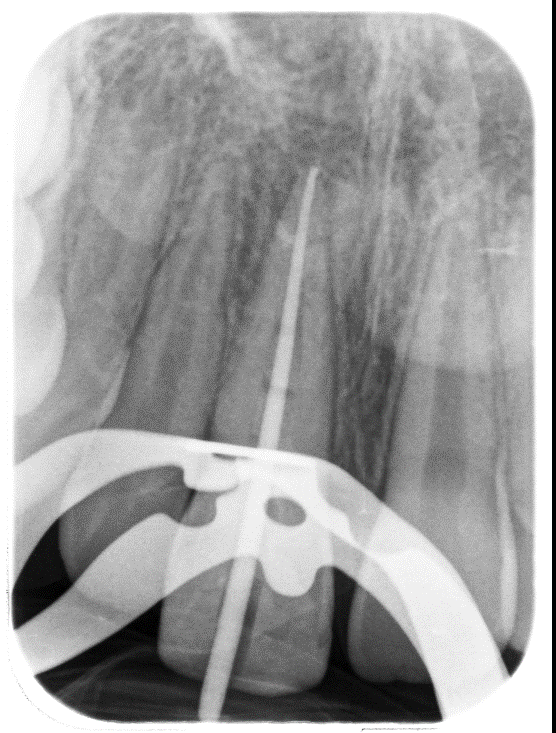

Working length established. Take care with irrigation and such a large canal!